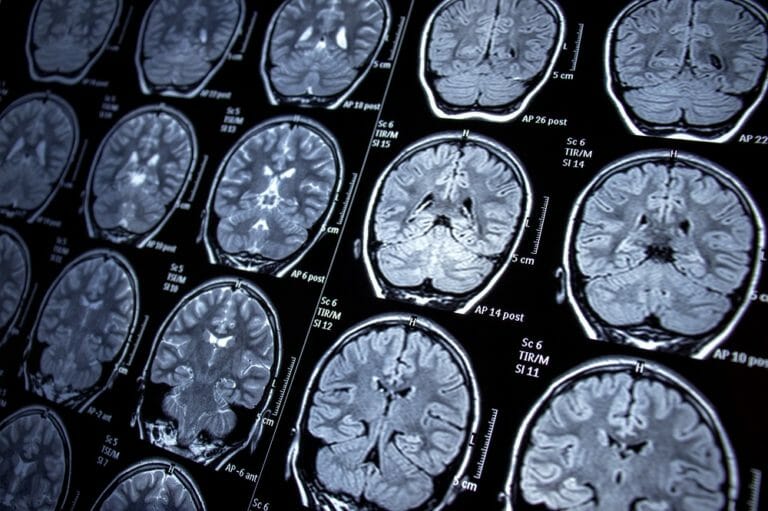

Uncovering the Neurological Substrates Underlying Restlessness in Cluster Headache – A Functional MRI Study

Functional MRI study from Taipei and Mayo Clinic identifies locus coeruleus–substantia nigra connectivity as the neural substrate of restlessness in cluster headache. CHICAGO — Restlessness